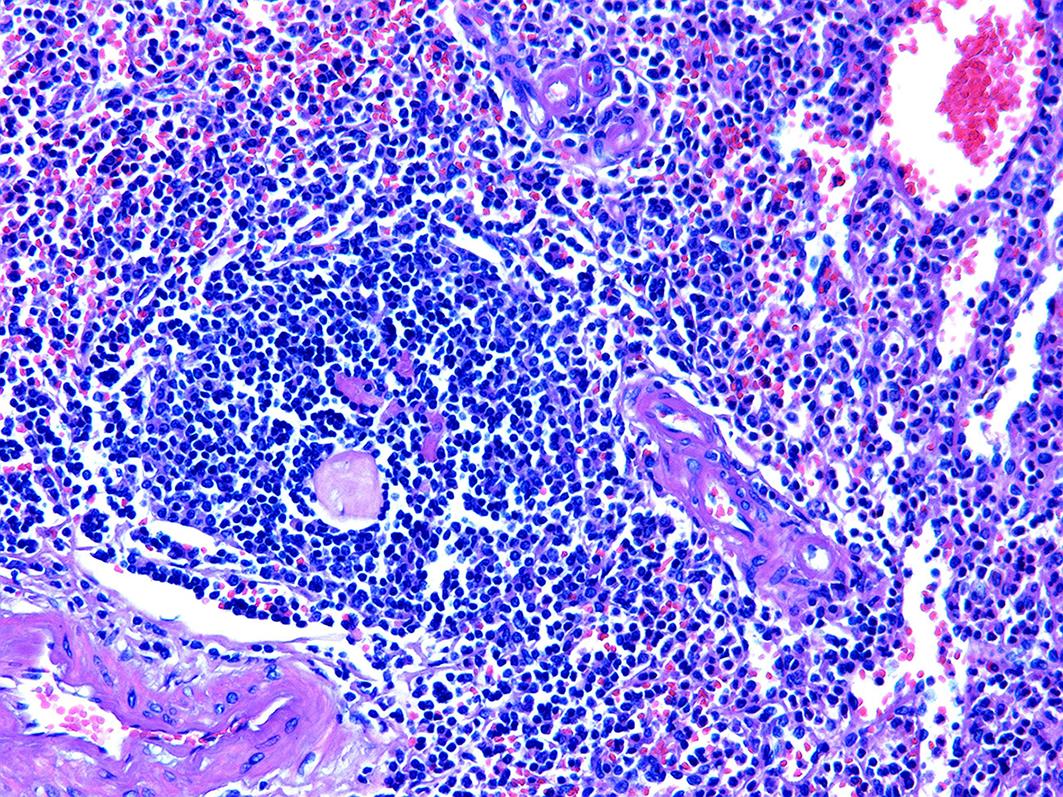

胰腺内副脾误诊2例报告

摘要(1364) HTML (331) PDF (1188KB)(158)

副脾是指正常脾脏以外存在的,与主脾结构相似,有一定功能的脾脏组织,其中完全被胰腺包裹的胰腺内副脾(IPAS)发生率仅为2%,因其临床症状不典型,影像学特征与胰腺神经内分泌肿瘤、胰腺实性假乳头状瘤以及其他胰腺占位性病变较为相似,临床上容易误诊。本文报道了2例分别被误诊为胰腺神经内分泌肿瘤和胰腺实性假乳头状瘤的IPAS患者,并分析误诊原因,总结诊疗经验,以期提升临床对IPAS明确鉴别诊断的认识。